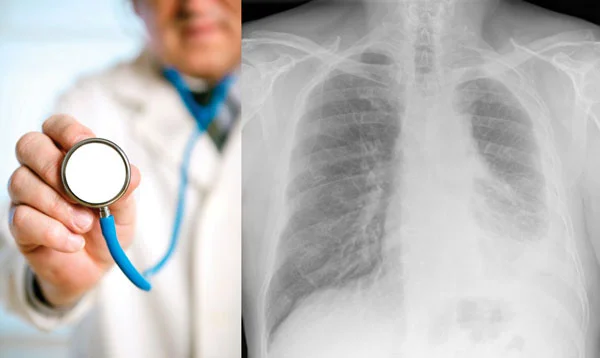

Mesothelioma: Understanding Risks, Exposure, and Early Detection Mesothelioma is a rare and aggressive cancer primarily linked to asbestos exposure. Historically, it was believed to affect mostly men, as men are four times more likely to develop mesothelioma due to occupational asbestos exposure in industries like construction, shipbuilding, and manufacturing. However, women are also at risk, … Read more

Malignant Mesothelioma: Causes, Symptoms, Diagnosis & Early Detection Malignant mesothelioma is a rare but aggressive cancer caused primarily by asbestos exposure. While it is often mistaken for lung cancer, malignant mesothelioma can also affect the abdominal cavity, heart lining, and even the testicles. In this article, we will explore the causes, symptoms, diagnosis, and importance … Read more